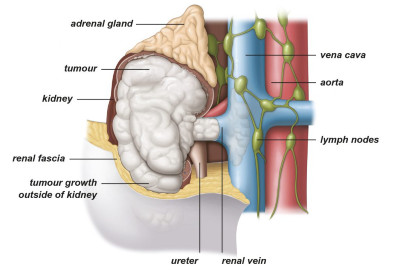

Εικ. 2 : Τα 4 στάδια του καρκίνου του νεφρού

Εντοπισμένο ονομάζουμε τον καρκίνο που εξακολουθεί να περιορίζεται εντός των ανατομικών ορίων του νεφρού, χωρίς να έχει επεκταθεί σε άλλες ανατομικές δομές, όπως λεμφαδένες ή άλλα όργανα (Εικ. 3,4).

Εικ. 3: Όγκος σταδίου Ι

Εικ. 4: Όγκος σταδίου ΙΙ

Εικ. 5: Όγκος σταδίου ΙΙΙ με επέκταση στη νεφρική φλέβα, στο περινεφρικό λίπος και στην κοίλη φλέβα

Εικ. 6: Όγκος σταδίου IV με επέκταση έξω από το νεφρό